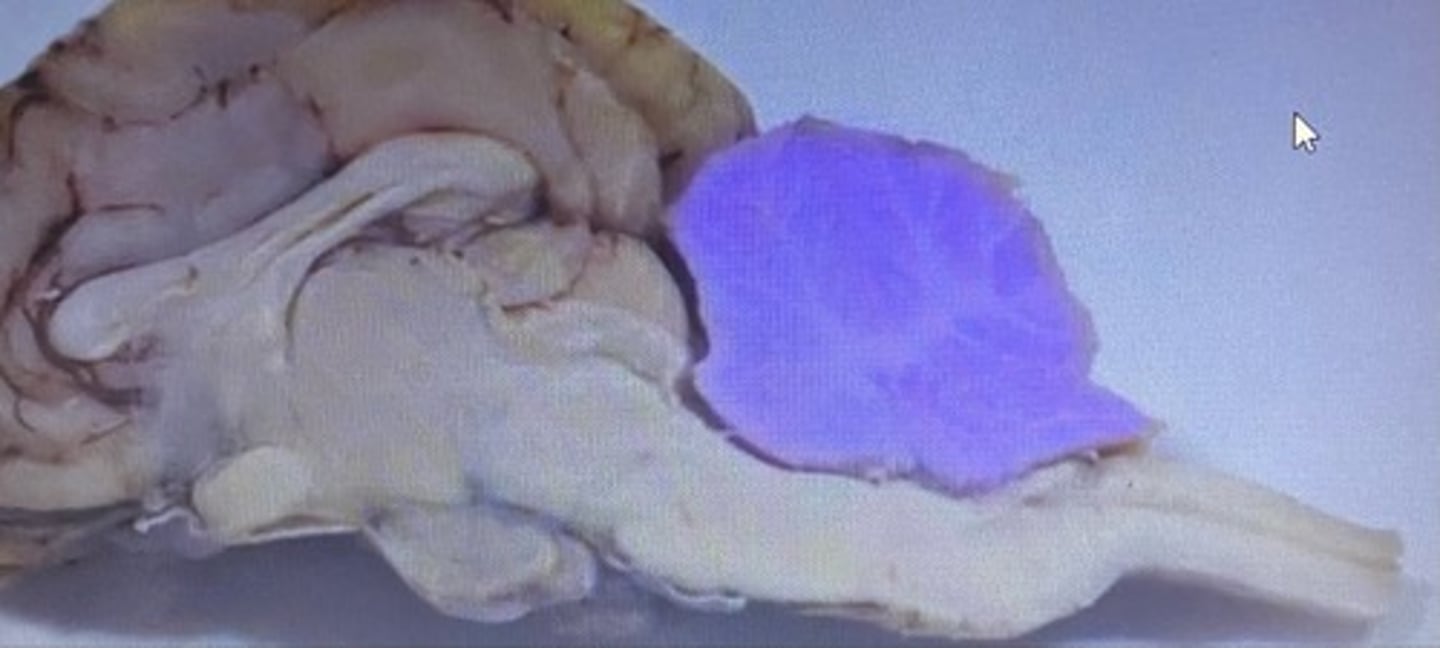

Cerebellum

Cerebellum

-coordinates muscles movements, muscle memory

Transverse Fissure

-separates cerebrum & cerebellum

Sheep Cerebellum